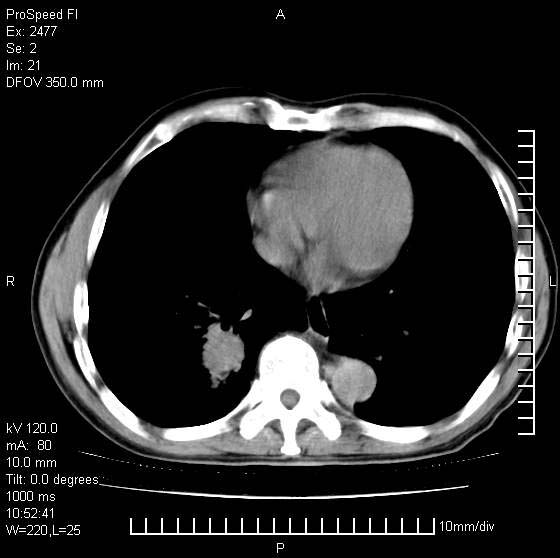

以下是引用天南地北在2007-10-9 14:29:00的发言:[br]1:右上肺结核[br]2:右肺下叶肿块:不支持肺癌,首先考虑炎性病变-肺脓疡可能性大[br]理由:1:临床病史支持,肺脓肿症状不明显应该是不规则服药造成。[br] 2:肿块边缘模糊,周围可见炎性渗出,长毛刺,内见支气管征,不过有点不规则。[br] 我感觉下肺癌这个诊断有点偏左,建议积极抗炎治疗后复查

以下是引用卜一在2007-10-9 15:55:00的发言:[br][br] [br] 1:右上肺结核[br]2:右肺下叶肿块:不支持肺癌,首先考虑炎性病变-肺脓疡可能性大[br]理由:1:临床病史支持,肺脓肿症状不明显应该是不规则服药造成。[br] 2:肿块边缘模糊,周围可见炎性渗出,长毛刺,内见空气支气管征,不过有点不规则。[br] 我感觉下肺癌这个诊断有点偏左,建议积极抗炎治疗后复查![br]支持! [br] [br] [br]

以下是引用wxy7406在2007-10-9 21:02:00的发言:[br]结合临床病史首先考虑感染性病变,但周围型肺癌不能除外,1.患者年龄偏大2.临床有咯血3.(也觉得是最重要的一点)病灶内有偏心性空洞。

以下是引用王仕学在2007-10-9 13:48:00的发言:[br]右下肺周围性肺癌可能性大,最好活检吧

以下是引用hhcckk在2007-10-9 15:18:00的发言:[br]右上肺病灶考虑结核,病灶多种形态并存(纤维化、增殖性病灶并存)[br]右下肺病灶比较难说,个人意见更趋向于“天南地北”的诊断----肺脓肿[br]1、病人有明显的寒战,高热,肿瘤病人很少出现[br]2、病灶周围的肺纹理走向柔和,没有肿瘤病灶常见的集束征[br]3、病灶边缘的毛刺较长,恶性肿瘤多为短毛刺[br]痰中血丝和病人的年龄是两个不利于良性肿块的因素,建议早点活检

以下是引用ydx_74在2007-10-9 15:53:00的发言:[br]右上肺结核,右下中心性肺癌可能大,肺门淋巴结肿大。